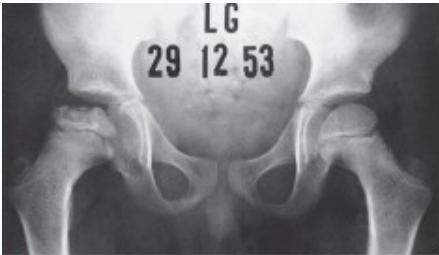

Radiographic Stages:

-

Initial/ Bone Death Stage - May initially appear normal on x-ray

- Increased density followed by collapse

Revascularization and Repair Stage - Reduced density and fragmentation on x-ray

Distortion and Remodeling Stage - Distortion, flattening (coxa plana)

- Enlargement (coxa magna) with partial uncoverage

Radiological Progression:

Progression: Sclerosis → Collapse → Fragmentation → Remodeling

Imaging Examples: